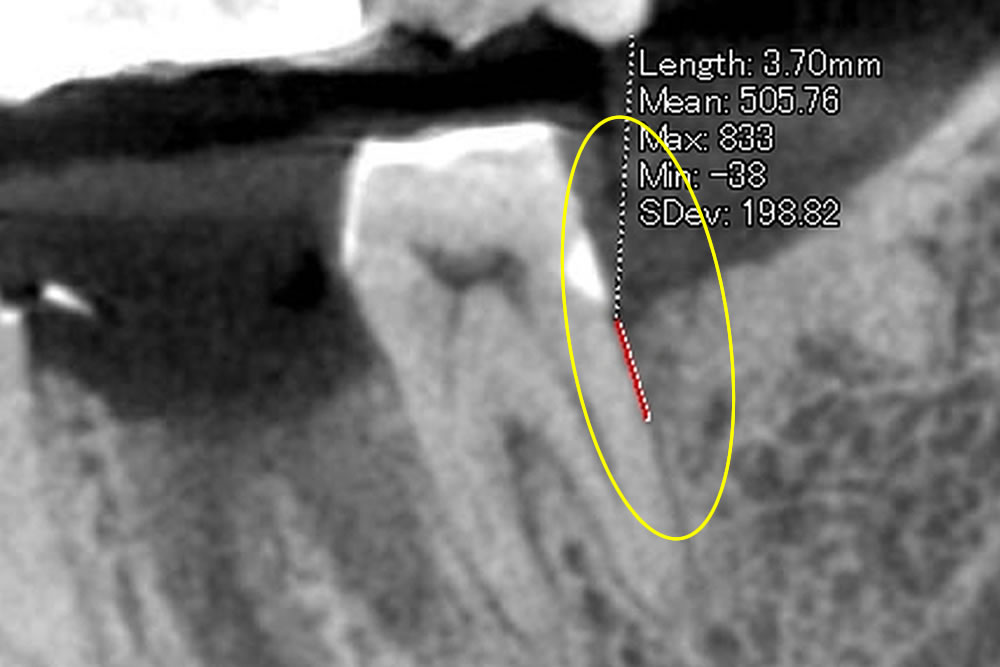

左下7番の奥側に、深い骨吸収(歯を支える骨が退縮している)を認めました。このままブリッジ治療を進めると、ただでさえ歯のない部分の負荷をうける一番後ろの歯が長持ちせず、せっかくのブリッジも駄目になってしまい、大切な奥歯を2本とも失ってしまう可能性が高くなります。

そのため、ブリッジが長く使えるように周りの骨をしっかりさせてから、被せていく計画となりました。

歯周再生療法の実施

欠損部の歯石、悪い歯肉を取り除いた後に、欠損部位に骨に変わるお薬を充填します。充填後にコラーゲンの膜で多い、患部を保護します。

⑤歯周再生療法実施後の骨の状態